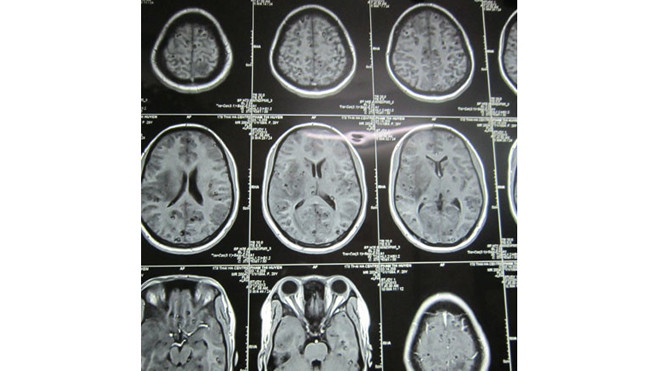

Những tổ sán kín đặc trong não bộ, những tổ sán lá gan âm thầm phá hủy gan của người bệnh… chỉ được nhìn thấy khi được chụp chiếu bằng kỹ thuật hiện đại. Các bệnh nhân thì bàng hoàng khi biết tình trạng của mình. Họ chưa bao giờ nghĩ, chỉ vì thói quen ăn uống mà tính mạng của họ bị những “kẻ thù ký sinh trùng” đe dọa.

Cả gia đình ông Đậu Đức Hựu, SN 1948 (Hoàng Mai, Nghệ An) chưa hết bàng hoàng khi kế lại trường hợp của ông. Ông Hựu bị lên cơn co giật cách đây đã 20 năm, năm đó ông khoảng gần 50 tuổi. Đi khám chỗ nào người ra cũng kết luận là ông bị động kinh. Ông điều trị động kinh đã 20 năm nay không khỏi, hết thuốc động kinh lại tiêm thuốc chống co giật. Cứ thỉnh thoảng, cơn co giật lại khiến ông và gia đình khổ sở, sợ hãi. Gần đây, ông Hựu nôn ra máu đông rồi bất tỉnh nhân sự. Bệnh viện cho rằng ông bị tai biến. Sau khi được chụp cộng hưởng từ tại bệnh viện tuyến tỉnh, các bác sĩ kết luận ông bị sán làm tổ trong não. Lúc này đã là tháng 4. 2016, những tổ sán ken kín trong não, chèn ép gây giãn não thất, ông Hựu phải phẫu thuật, hút dịch trong não rồi mới có thể điều trị tẩy sán được.

Theo các bác sĩ tại Viện Sốt rét - Ký sinh trùng - Côn trùng TƯ, bệnh nhân mắc sán não sẽ bị đau đầu, tê tay, co giật nên một số bác sĩ ở các địa phương, thậm chí ở trung ương họ không nghĩ đến ký sinh trùng. Ths.BS Trần Huy Thọ - Trưởng khoa Điều trị, Viện Sốt rét - Ký sinh trùng - Côn trùng Trung ương cho biết: “Chúng tôi tiếp nhận nhiều bệnh nhân đã khám ở ở nhiều nơi rồi. Bệnh nhân bị sán não co giật nhiều, động kinh, đi khám các nơi được chẩn đoán và điều trị triệu chứng động kinh nhưng không thể khỏi được do chưa tìm ra căn nguyên của bệnh. Có rất nhiều bệnh nhân đã từng uống các loại thuốc điều trị động kinh (thuốc hướng thần). Có người uống nhiều đến mức lơ mơ, đi lại giật giờ như người bị tâm thần”.

“Một năm chúng tôi tiếp nhận mấy trăm ca sán não. Đây là căn bệnh hết sức bình thường mà người dân có thể mắc phải. Nó vô cùng nguy hiểm, nhưng người dân lại coi thường, không chú ý giữ gìn”.

Năm 2015, Khoa Điều trị, Viện Sốt rét - Ký sinh trùng - Côn trùng Trung ương tiếp nhận hơn 5.000 ca đến khám và điều trị. Năm 2016, con số đã tăng lên thành 7.000 ca. Chỉ riêng 6 tháng đầu năm, Viện đã tiếp nhận 5.444 ca nhiễm bệnh do ký sinh trùng. Nhiều nhất là bệnh nhân mắc sán não, sán lá gan, giun đũa chó…